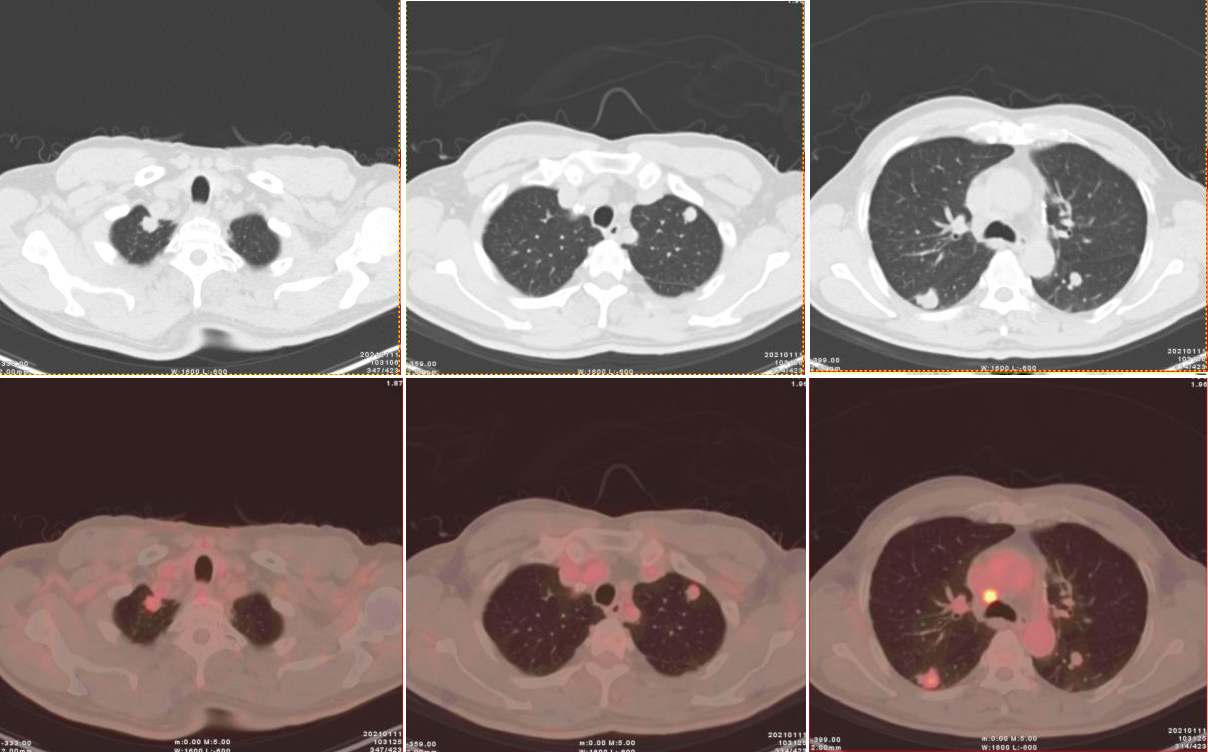

圖2、3:(上為CT橫斷位圖像,下為橫斷位融合圖像):雙肺多發(fā)結(jié)節(jié),部分可見淺分葉,邊緣可見段毛刺,代謝輕度增高。

雙肺見多發(fā)散在大小不一實性結(jié)節(jié),邊界尚清,形態(tài)不規(guī)則,部分邊緣見短棘突及淺分葉,密度不等,CT 值約19~30Hu,大者位于右肺下葉背段,大小約 1.7×1.8×2.1cm;部分病灶放射性攝取輕度增高,早期 SUVmax 3.47,1小時延時顯像示病灶放射性攝取有所減低,SUVmax 2.1。

PACC為低度惡性腫瘤,較常見的肺癌 (如鱗狀細(xì)胞癌)預(yù)后好,但在CT上,PACC無明顯特異性表現(xiàn),與常見的肺癌類型無法鑒別。本例中雙肺十幾個結(jié)節(jié)中部分病灶呈現(xiàn)放射性攝取輕度增高,早期SUVmax 3.47,1小時延時顯像示病灶放射性攝取有所減低,SUVmax 2.1,與其低度惡性的病理類型一致。

此例為雙肺多發(fā)腺樣囊性癌,更屬罕見,診斷難度極大。通過耐心分析每一個結(jié)節(jié)的特點,發(fā)現(xiàn)其都呈現(xiàn)略有分葉毛刺的形態(tài),不似轉(zhuǎn)移瘤常見的類圓形、邊緣光滑的結(jié)節(jié);全身PET/CT未見其他組織器官的占位性病變或高代謝灶,因此不考慮雙肺轉(zhuǎn)移瘤;此外,雙肺多發(fā)結(jié)節(jié)邊緣無炎性病變的滲出性改變,亦未見結(jié)核常見的鈣化及衛(wèi)星造,代謝上沒有肺淋巴瘤常見的顯著增高。